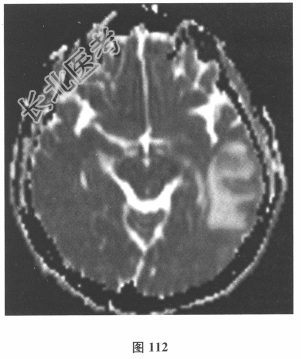

脑脊液检查:常规、生化均正常,CSF-病毒TORCH(-),抗Hu、Yo、Ri均阴性,OB、MBP正常。血清抗Hu、Yo、Ri均阴性。颅脑MRI显示左颞枕、右顶枕多发长T₁、长T₂信号,Flair高信号,病变累及皮质及皮质下白质,病灶无强化,见图108~图114。)根据颅脑MRI,需要鉴别的疾病应是